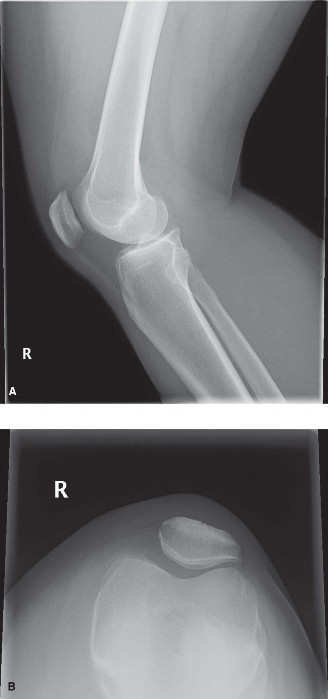

CASE 1 A 22-year-old, female jogger presents complaining of right knee pain. She describes an insidious onset of her symptoms during the last 3 months. She enjoys running most days and is training for a five-mile road race. Recently, she has been running more and has added hill training. Her pain is centered around the patella with little swelling. She has crepitus and pain when climbing stairs or getting out of a chair. X-rays are shown in Figure 9–1A–C.

Figure 9–1 A–B

Figure 9–1 C